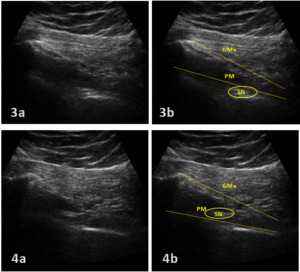

MSK US involves the use of a high-frequency linear transducer to obtain detailed images of the targeted area. When examining the PM using ultrasound, the patient should first assume the prone or lateral decubitus position to best visualize the PM and sciatic nerve.1 Placing a pillow or towels between the bed and the patient’s inguinal area can help increase the pelvic tilt. This allows better visualization of the PM via ultrasound. A curvilinear transducer is placed in a transverse orientation to first identify the sacral cornua and is then moved toward the greater trochanter until the lateral edge of the sacrum is observed. The transducer is moved further laterally until the greater trochanter and ilium are both observed (Fig. 1). The PM will appear as a hyperechoic band lying between the lateral edge of the sacrum and the greater trochanter and deep in the gluteus maximus muscle. The sciatic nerve appears as an oval shaped hypoechoic structure lying deep in the PM (Fig. 2).